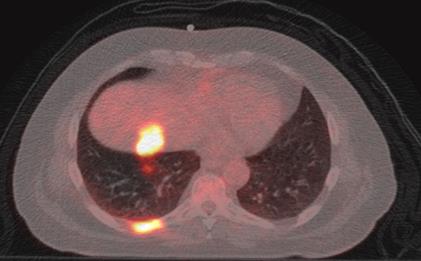

At our institution, lung cancer accounts for 37% of all PET-CT scans performed.

The evidence-based indications for use of PET-CT in the UK 2016 list five indications for FDG PET CT in lung cancer.